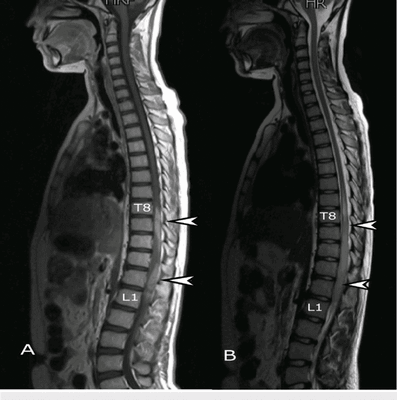

Гемангиомы на магнитно-резонансной томографии грудного отдела позвоночника (сагиттальная проекция, Т2 взвешенная последовательность)

МРТ позвоночника - высокоинформативный метод диагностики, использующий для построения детальных изображений структур области интереса свойства магнитного поля, радиоволны и компьютерную обработку. По показаниям исследование выполняют с контрастным усилением: в вену вводят препарат, содержащий хелаты гадолиния.

Магнитно-резонансное сканирование пояснично-крестцового отдела позвоночника: множественные гемангиомы (сагиттальная плоскость, Т1 ВИ)